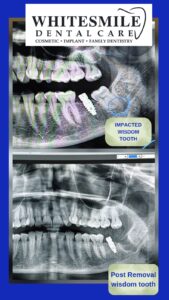

π¦· Wisdom Tooth Extraction with Pre & Post OPG Scan

πΈ The Role of OPG Scan in Wisdom Tooth Extraction

An OPG (Orthopantomogram) is a high-resolution panoramic dental X-ray that provides a complete overview of:

π¦· All teeth (upper & lower)

π¦· Jaw bones

π¦· Wisdom tooth position & angulation

π¦· Nerve pathways

π¦· Sinuses

π¦· Existing dental treatments

π Why Pre-OPG Scan Is a Game-Changer

At White Smile Dental Care, every wisdom tooth extraction begins with a detailed OPG scan because it allows us to:

β Precisely locate impacted teeth

β Identify nerve proximity

β Reduce surgical risks

β Plan a minimally invasive procedure

β Avoid post-surgical complications

2οΈβ£ Digital Pre-Operative OPG Scan πΈ

The scan helps us:

β Evaluate tooth position

β Map nerve pathways

β Design a safe surgical plan

5οΈβ£ Post-Operative Care & OPG Confirmation πΈ

A post-removal OPG scan may be advised to:

β Confirm complete extraction

β Monitor healing

β Ensure no residual pathology

πΈ Importance of Post-Extraction OPG Scan

A post-removal OPG scan helps:

β Confirm complete tooth removal

β Evaluate bone healing

β Rule out complications

β Plan future implants or orthodontics